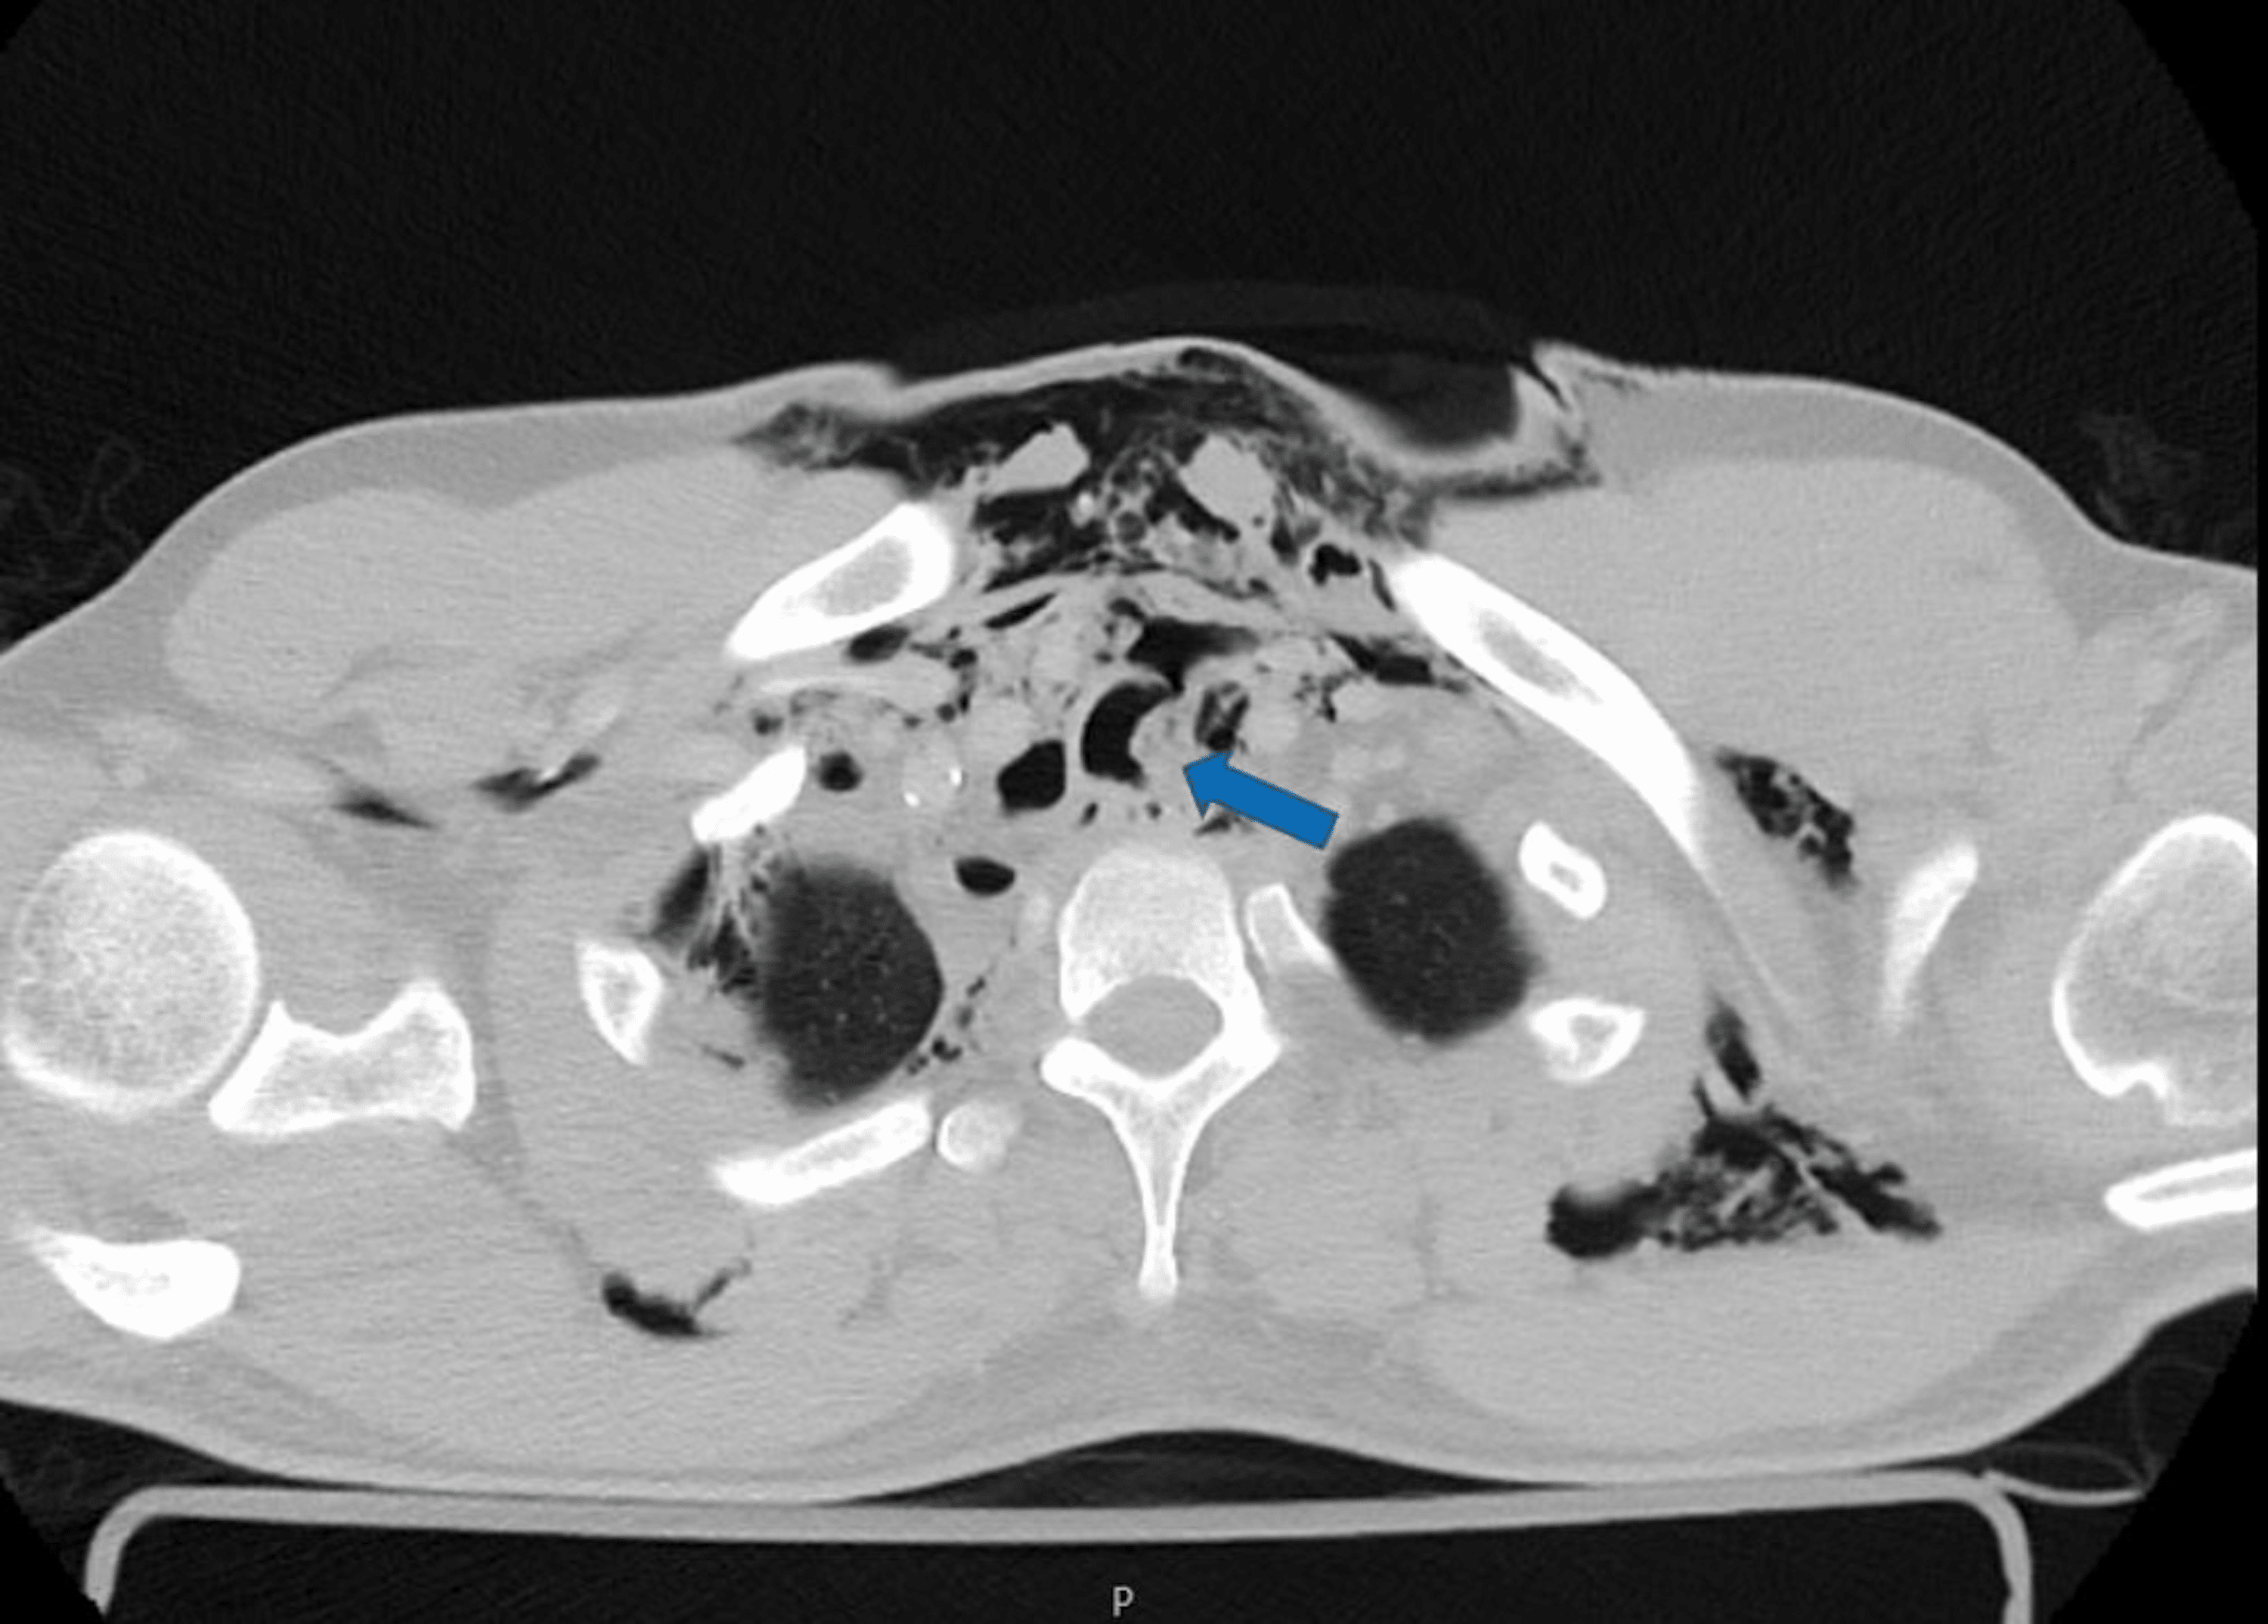

Thoracic CT showing posterior tracheal rupture (Arrow). Download Tracheal Rupture The major causes of tracheal injury include iatrogenic, blunt trauma, penetrating trauma, inhalation and aspiration of liquids or objects. Tracheobronchial tears are uncommon injuries or lacerations or puncture occurring anywhere in the tracheobronchial tree resulting from penetrating or blunt trauma to the neck or. Common etiologies include blunt or penetrating. A tracheal or bronchial rupture is a tear or break. Tracheal Rupture.